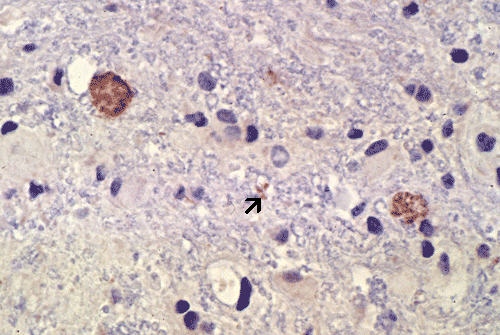

Toxoplasma cyst, immunohistochenistry: Although the cysts can be easily identified by hematoxylin and eosin stain, immunohistochemisty is very helpful in confirming the identity and the bradyzoites (arrow).